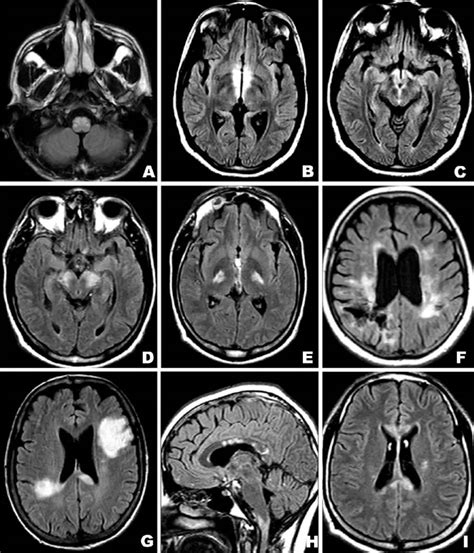

Let’s dive into understanding pseudoischemic brain lesions. Pseudoischemic brain lesions are fascinating yet complex phenomena in the realm of neurology. Often mimicking the signs and symptoms of an actual stroke or ischemic event, these lesions present a diagnostic challenge. They appear on imaging studies like CT scans or MRIs as if there’s been a lack of blood flow to the brain, but in reality, the underlying cause is something else entirely . This “something else” can range from migraines to seizures, and even certain metabolic disorders. Recognizing and differentiating pseudoischemic lesions from true ischemic events is crucial for proper patient management and treatment. Understanding the nuances of these lesions requires a comprehensive grasp of neuroimaging, clinical presentations, and potential underlying etiologies.

When we talk about pseudoischemic lesions , we’re not just dealing with a single entity. The appearance of these lesions can vary significantly based on the cause and the area of the brain affected. For instance, a lesion caused by a migraine might look different from one caused by a seizure. Moreover, the location of the lesion plays a critical role in determining its potential impact . Lesions in eloquent areas of the brain, such as those controlling speech or motor function, can lead to noticeable deficits, while lesions in less critical areas might be asymptomatic. Therefore, a detailed analysis of the lesion’s characteristics, combined with a thorough clinical evaluation, is essential for accurate diagnosis and management. It’s like being a detective, piecing together clues to solve a medical mystery! The clinical presentation of a patient with a pseudoischemic lesion can be quite varied. Some individuals may experience stroke-like symptoms such as sudden weakness, numbness, speech difficulties, or visual disturbances. Others may present with symptoms more commonly associated with migraines or seizures, such as headaches, auras, or convulsions. What makes it even more challenging is that these symptoms can sometimes overlap, making it difficult to distinguish between a true ischemic event and a pseudoischemic lesion . Therefore, a detailed medical history, neurological examination, and careful consideration of the patient’s risk factors are crucial in narrowing down the possibilities. Think of it as creating a differential diagnosis, where you list all the potential causes and then systematically rule them out based on the available evidence.

When considering diagnostic approaches, neuroimaging plays a pivotal role. Neuroimaging techniques are essential in diagnosing pseudoischemic lesions . Magnetic resonance imaging (MRI) is generally the preferred imaging modality due to its superior sensitivity and ability to detect subtle changes in brain tissue . MRI can provide detailed information about the location, size, and characteristics of the lesion, as well as identify any underlying abnormalities such as edema or inflammation. Diffusion-weighted imaging (DWI) is a specific MRI technique that is particularly useful in distinguishing between true ischemic lesions and pseudoischemic lesions . DWI measures the movement of water molecules in the brain tissue. In true ischemia, DWI typically shows a characteristic pattern of restricted diffusion, indicating a lack of blood flow. In contrast, pseudoischemic lesions may not show this pattern, or the pattern may be different, helping to differentiate them from true ischemia.

Computerized tomography (CT) scans can also be used in the evaluation of pseudoischemic lesions , although they are generally less sensitive than MRI. CT scans are particularly useful in the acute setting to rule out other potential causes of stroke-like symptoms, such as hemorrhage or mass lesions . However, CT scans may not be able to detect subtle changes associated with pseudoischemic lesions, particularly in the early stages. In addition to neuroimaging, other diagnostic tests may be necessary to determine the underlying cause of a pseudoischemic lesion . An electroencephalogram (EEG) can be used to assess for seizure activity, particularly in patients with a history of seizures or who present with symptoms suggestive of seizures. Blood tests may be performed to check for metabolic abnormalities, such as hypoglycemia or hyperglycemia, or to evaluate for inflammatory or infectious conditions. In some cases, a lumbar puncture may be necessary to analyze the cerebrospinal fluid (CSF) for signs of infection or inflammation . The diagnostic approach to pseudoischemic lesions should be individualized based on the patient’s clinical presentation, medical history, and risk factors. A thorough evaluation, including a detailed neurological examination, neuroimaging studies, and potentially other diagnostic tests, is essential to determine the underlying cause of the lesion and guide appropriate management. It’s like putting together a puzzle, where each piece of information helps to complete the picture.